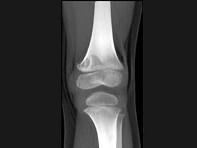

问题 男,12岁,大腿下部间歇性疼痛,劳累后加重,结合图像,最可能的诊断是?(?)

选项 A.纤维性骨皮质缺损 B.干骺端结核 C.骨样骨瘤 D.邻皮质软骨瘤 E.非骨化性纤维瘤

答案 A